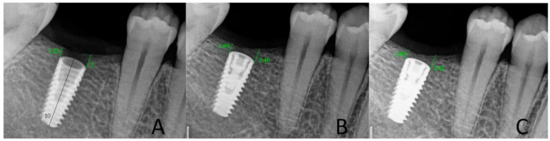

2.4. Radiological Assessment of the Bone Level in the Proximity of the Implant